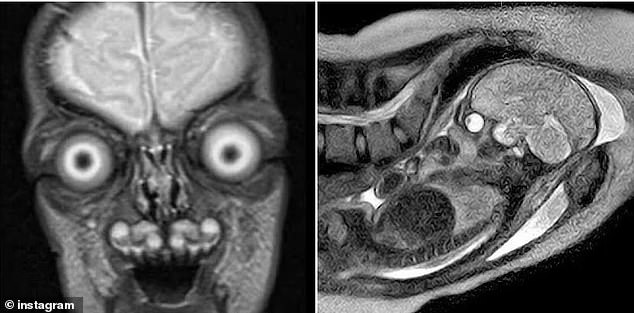

Disturbing images of fetal MRI scans have sparked renewed public debate about the safety of performing magnetic resonance imaging on pregnant women. These images, which reveal the skeleton of an unborn baby in stark white against darker soft tissue, have circulated online, prompting concern and curiosity among expectant mothers and the general public. The clarity of the scans, which can show individual finger bones, the full spine, and even the skull, has left some viewers unsettled, questioning the potential risks of the procedure.

Public reactions to viral MRI images have been mixed. Some describe the scans as terrifying, while others find them fascinating or even amusing. Comments on social media range from expressions of disbelief—such as 'What the hell is this gang?'—to emotional responses like 'That's definitely not a human baby.' These reactions highlight the psychological impact of the images, which can be both revealing and unsettling for expectant parents.